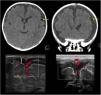

Macrocephaly is a clinical term defined as an occipitofrontal circumference more than two standard deviations above the mean. It is present in 5% of children and is a common indication for imaging studies. There are multiple causes of macrocephaly; most of them are benign. Nevertheless, in some cases, macrocephaly is the clinical manifestation of a condition that requires timely medical and/or surgical treatment. The importance of imaging studies lies in identifying the patients who would benefit from treatment. Children with macrocephaly associated with neurologic alterations, neurocutaneous stigmata, delayed development, or rapid increase of the circumference have a greater risk of having disease. By contrast, parental macrocephaly is predictive of a benign condition. Limiting imaging studies to patients with increased risk makes it possible to optimize resources and reduce unnecessary exposure to tests.